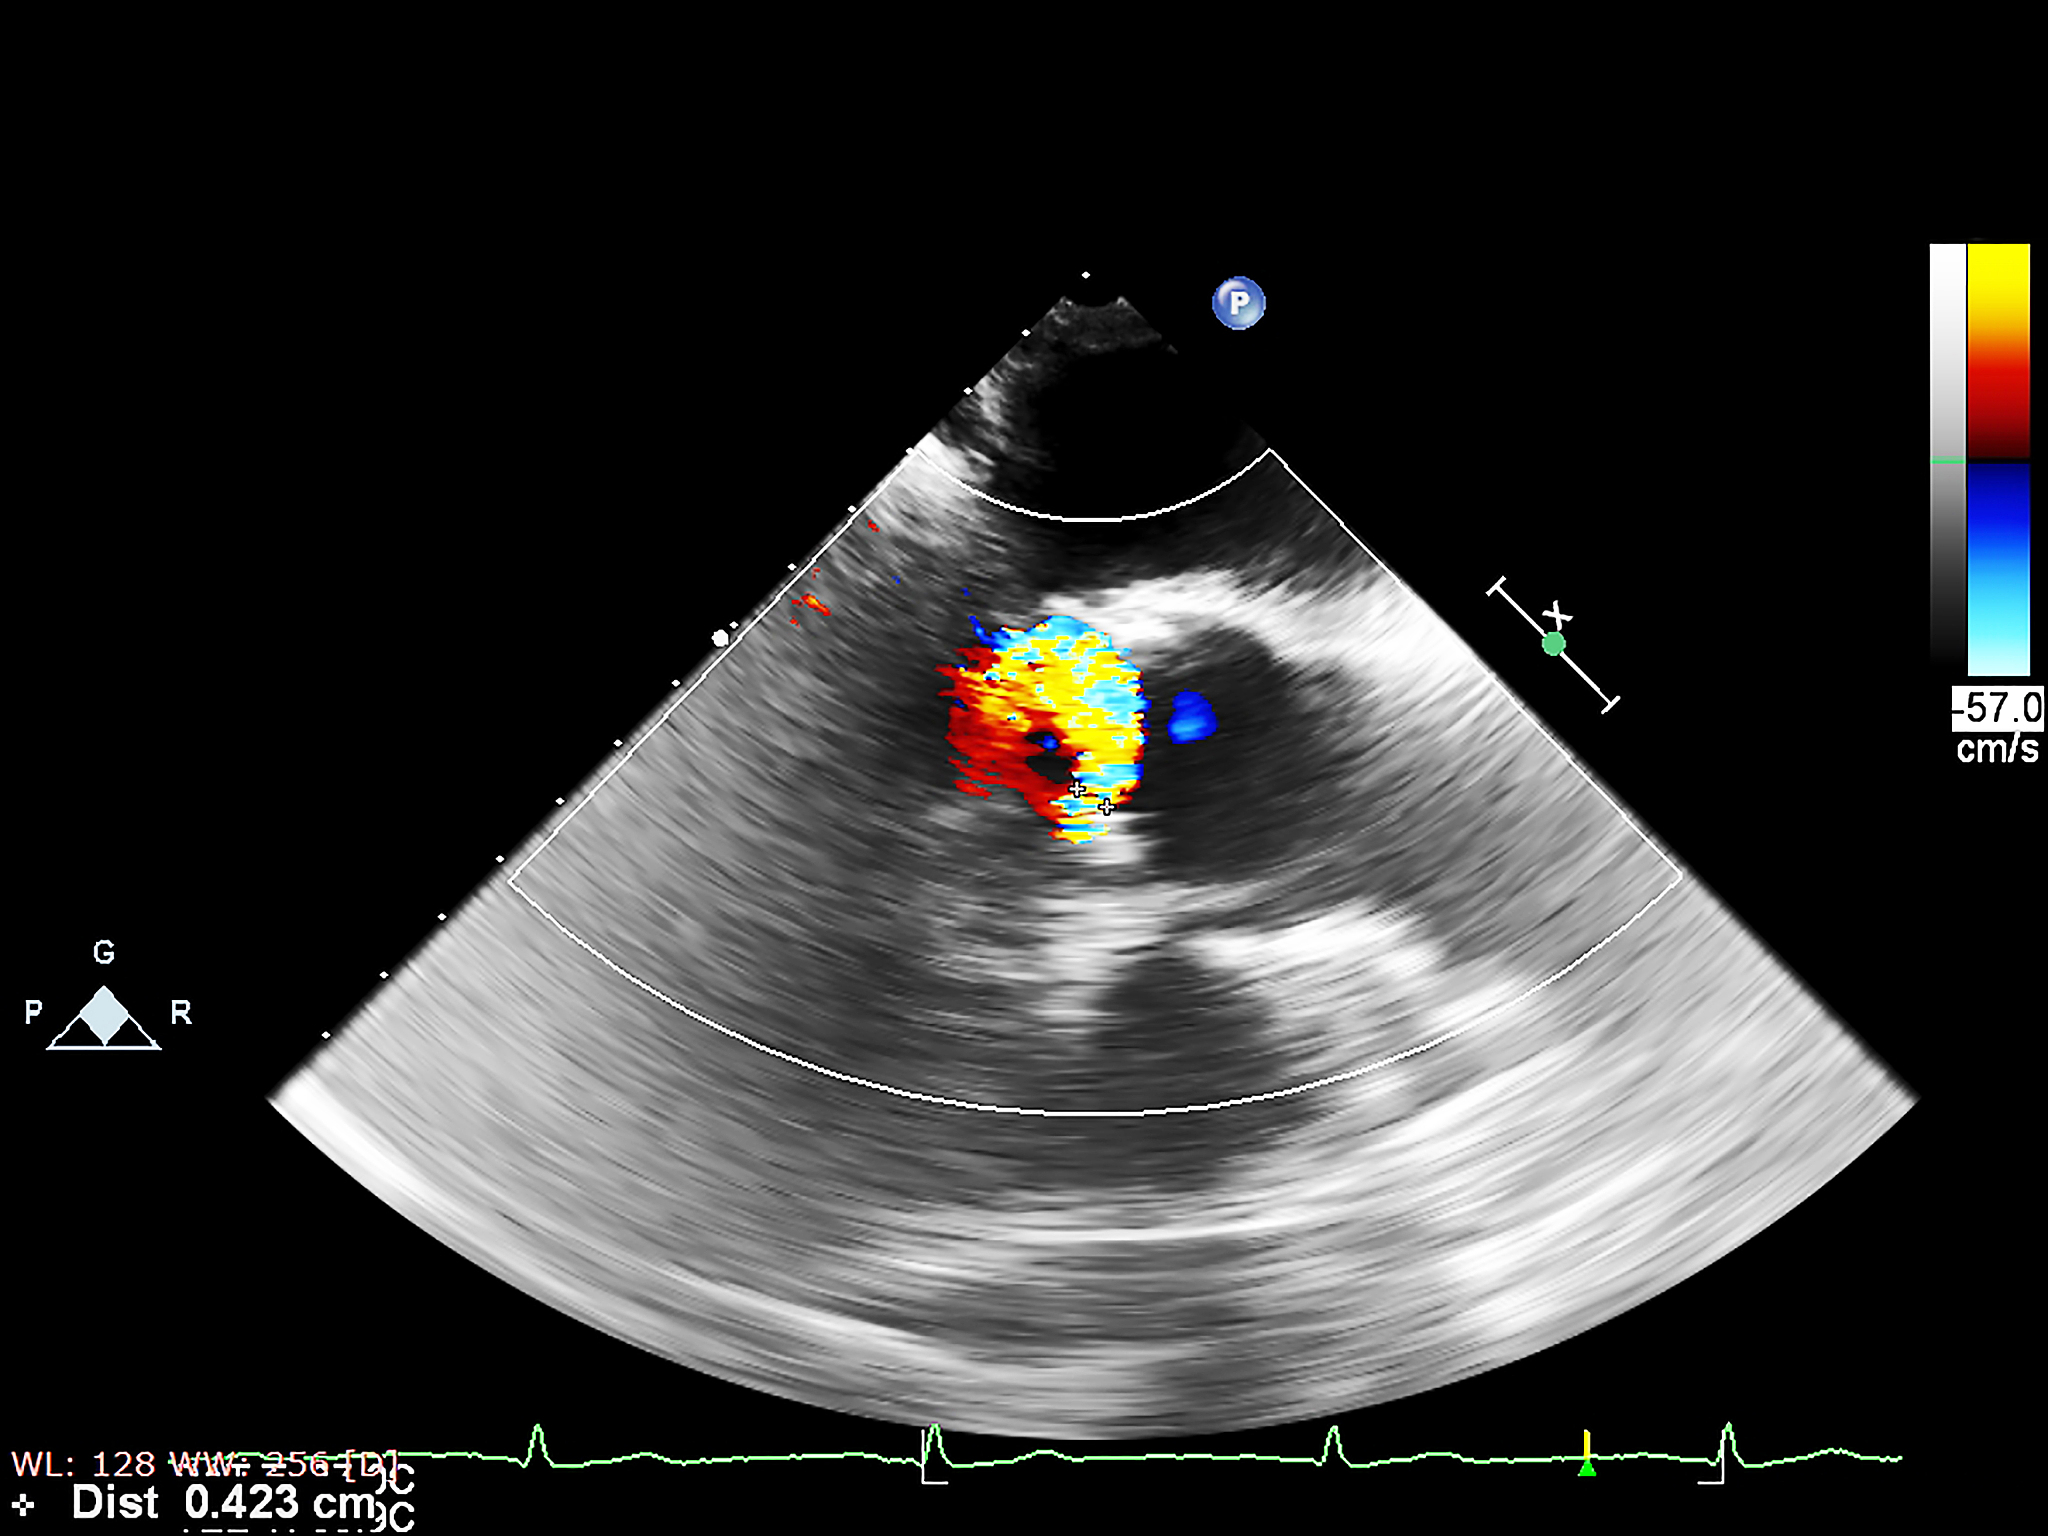

随着医学技术的不断发展,医学领域的治疗手段也在不断更新。超声间质热消融技术便是其中的一种。该技术是一种非侵入性的治疗手段,适用于多种疾病的治疗,如肝肿瘤、肾癌、骨肿瘤等。该技术的原理是利用高频声波产生的热能将病灶部位的细胞组织烧灼并摧毁,从而达到治疗的效果。与传统的手术治疗相比,超声间质热消融技术具有创伤小、恢复快、疗效显著等优点,已经成为现代医学领域中不可或缺的治疗手段之一。本文将从超声间质热消融技术的原理、适应症、应用前景等方面进行探讨,以期为读者提供更深入的了解。

超声间质热消融技术:原理、适应症及应用前景